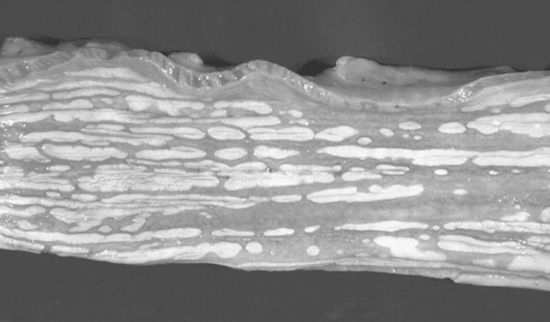

The equine incisors and molarized cheek teeth are hypsodont and have long anatomic crowns. The tooth crown is the enamel-containing portion of the tooth. When these hypsodont teeth erupt, their occlusal surface is covered with thin layers of cementum and enamel, which wear away from masticatory forces and abrasive forage, to expose the true or functional occlusal surface of the tooth. This process is termed coming into wear. The functional occlusal surface of hypsodont teeth is composed of thin, brittle sheets of hard enamel sandwiched between softer layers of cementum and dentin. This three-textured occlusal surface is self-sharpening and resistant to wear and fracture. The occlusal surfaces of the molar arcades wear in an undulating fashion with 13 loph basins (food channels) between transverse ridges.

The incisors and upper cheek teeth have enamel invaginations in the crown, termed infundibula. These enamel invaginations are partially filled with cementum, which receives its blood supply from the soft tissue covering the tooth before eruption. The shallow infundibulum present on each incisor has a wide opening at the occlusal surface, referred to as a “cup.” As the incisor wears, the small apical portion of the infundibulum eventually becomes exposed at the occlusal surface and is termed “the spot.” Each upper cheek tooth has a rostral and a caudal infundibulum. These enamel invaginations, or cones, give the central area of these teeth a hard wear surface. The center of the cement lake that fills the infundibulum contains a hole, which is the remnant (i.e., a “ghost”) of the central blood vessel that once supplied nutrition to the now dead infundibular cementum.

Much of the crown of the hypsodont teeth of the horse is held in reserve subgingivally, in the alveolar bone. The apex of the tooth slowly completes its development by forming roots for several years after the tooth erupts. The interior of the tooth is composed primarily of dentine, with primary dentine lining the common pulp chamber of the newly erupted hypsodont tooth. The pulp chambers of hypsodont teeth are active throughout the horse’s life and continuously produce secondary dentine within the pulp cavity. Continuous production of secondary dentine prevents the vital pulp from being exposed at the occlusal surface as the tooth wears. The depth of secondary dentine at the occlusal surface of the pulp horns varies in horses but is at least 5 to 7 mm thick and generally increases in thickness as the tooth ages. Secondary dentine absorbs pigment from feed and is seen as a brown area on the occlusal surface of the tooth.

The pulp cavity of the young, permanent cheek tooth is large, but as the tooth ages the pulp divides into smaller pulp chambers, or horns, by deposition of secondary dentine. From 2 to 4 years after eruption, mandibular cheek teeth have a distinct, apically located, common pulp chamber that communicates with the pulp horns. Five pulp horns are present in the 07s to 10s, six pulp horns are present in the 06s, and six or seven pulp horns are typically present in the 11s (Fig. 32-15). By 6 to 8 years after a mandibular cheek tooth erupts, production of secondary dentine divides the endodontic system of the tooth into two distinct compartments or roots. Each compartment consists of a root canal, a pulp chamber, and two or three pulp horns. Each maxillary cheek tooth has three roots. Because of the continuous production of cementum around the apical or root portion of the tooth and continuous wear of the crown, old equine teeth are primarily composed of cementum. When most of the enamel of the crown has worn away, the softer dentine and cementum are quickly worn flat, leading to the condition known as “smooth mouth.”44